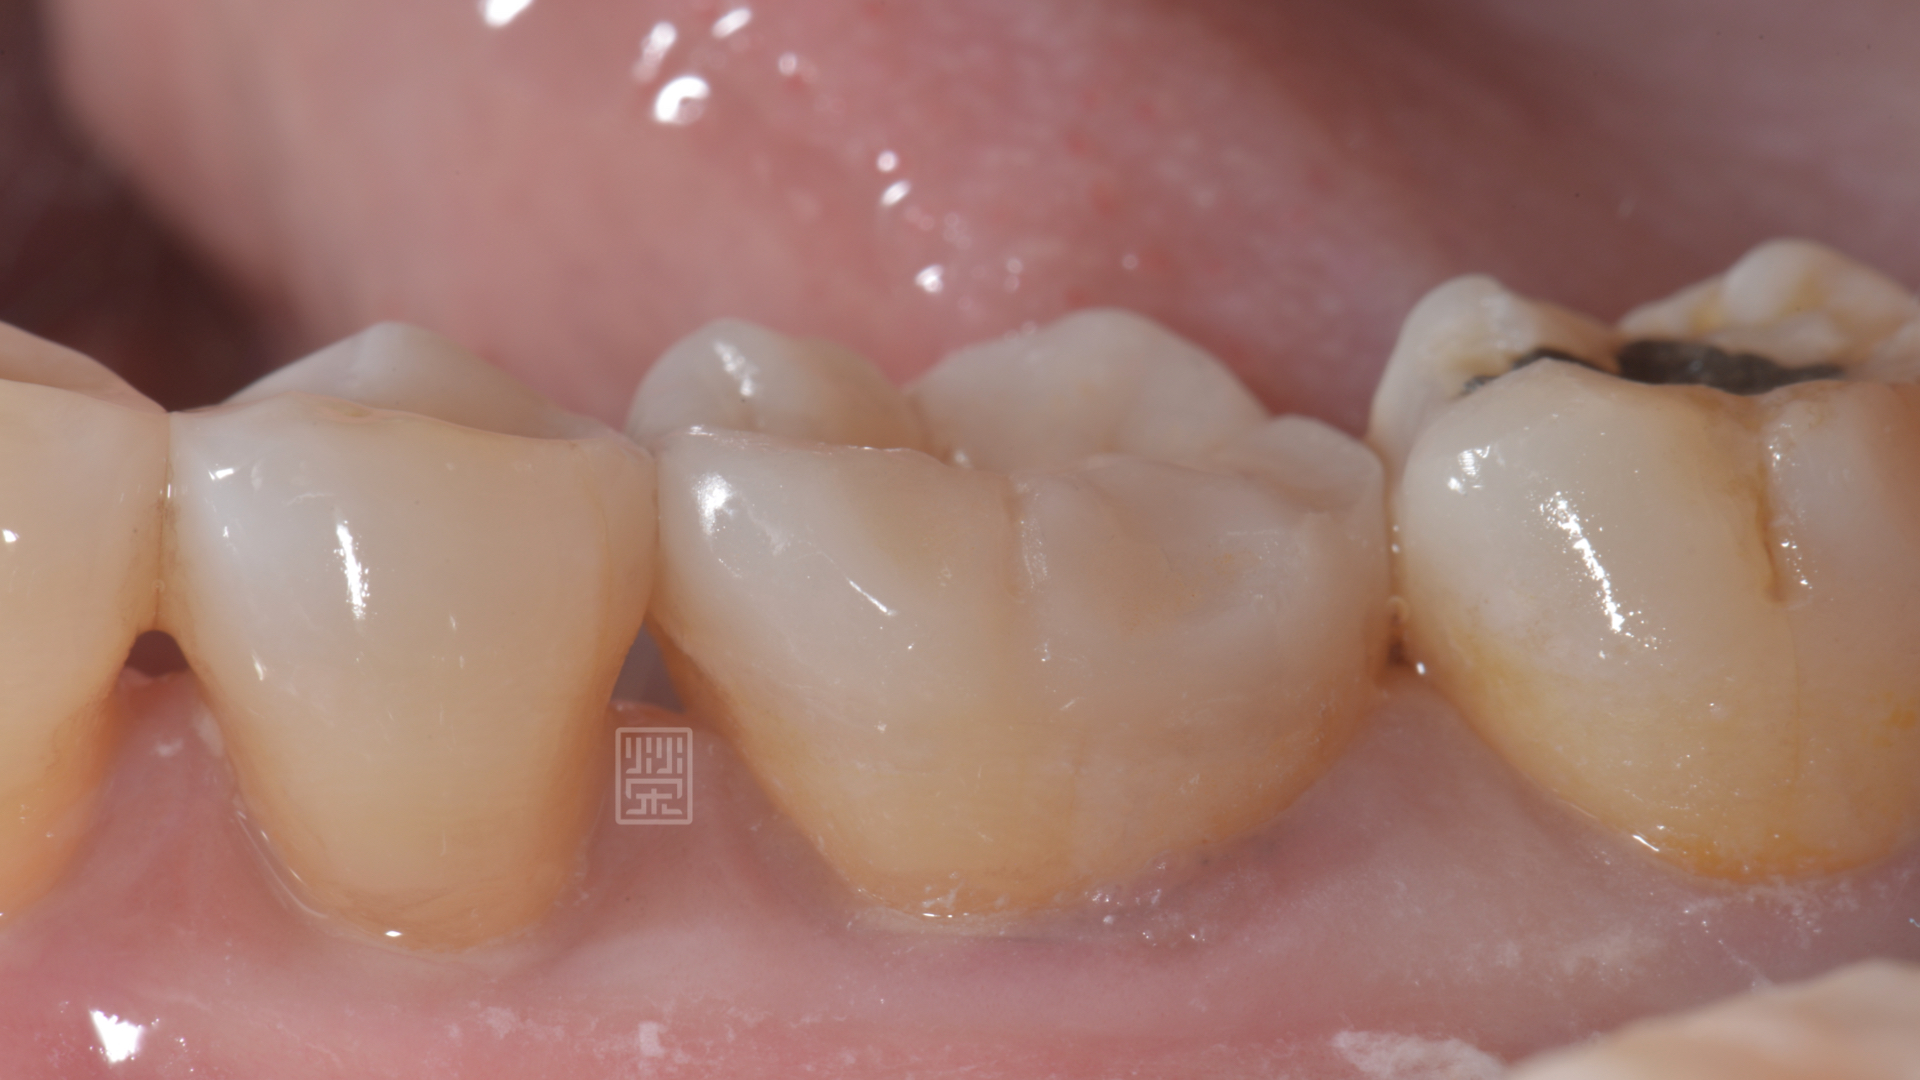

頰側有裂痕